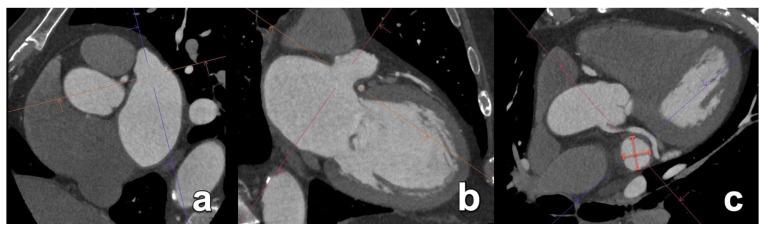

在过去十年中,多项试验和观察性研究证实,微创心脏介入治疗作为各种心脏病的可行治疗选择是有效的。在某些患者群体中,用于严重主动脉瓣狭窄的经导管技术已迅速成为外科主动脉瓣置换术的替代方法。此外,针对影响其他心脏瓣膜(如二尖瓣)的病症,非手术治疗选择也有所增加。这些新兴的微创介入治疗补充了已成熟的血管内技术,用于治疗心房颤动患者的房间隔缺损封堵、左心耳封堵和肺静脉隔离等疾病。鉴于这些手术的非手术性质以及缺乏对目标解剖结构的直接可视化,这些手术严重依赖精确的术前放射影像学检查,以实现最佳的患者选择和手术成功。本文基于作者的专家意见和详尽的文献研究。本手稿回顾了最常用的微创心脏介入治疗,强调了术前成像的基本信息以及放射学报告中必须包含的关键方面,以减少潜在并发症。准确的术前成像对于确保微创心脏介入治疗的安全有效至关重要,这突出了放射科医生在这些患者术前检查中的重要性。